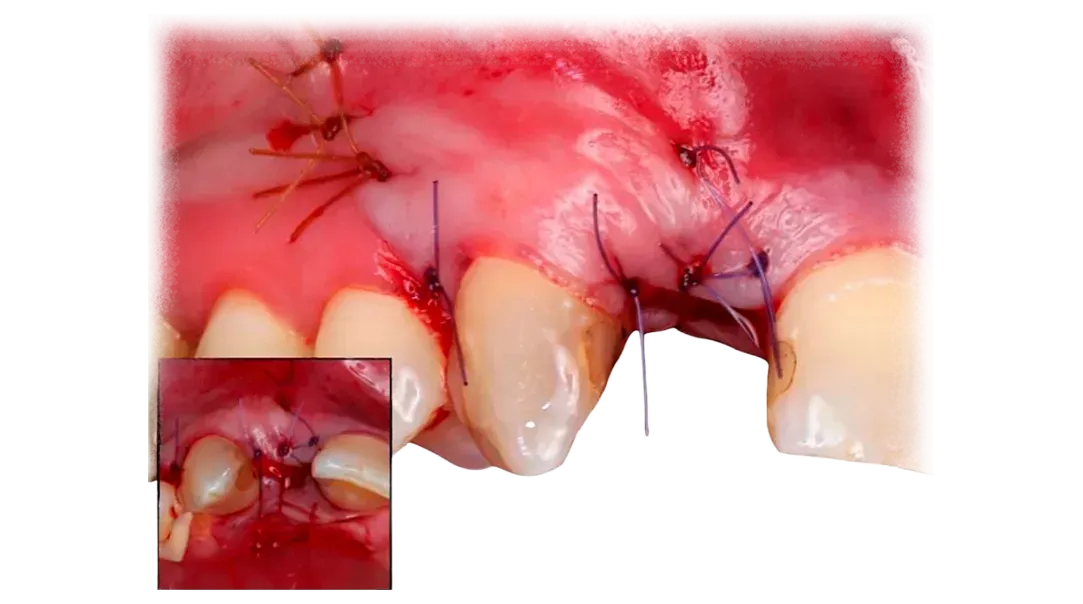

Successful regeneration depends on the interaction between biology, surgical technique, and biomaterial selection.

Key factors include maintaining space for bone formation, stabilizing graft materials, protecting the regenerative environment with appropriate membranes, and achieving stable soft tissue closure.

This program reviews these elements in detail so clinicians can approach GBR procedures with greater clarity in both planning and execution.